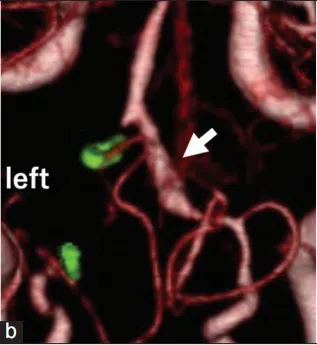

40多岁日本男性,出现轻微头疼并持续2天,但并无任何其他神经系统缺陷,CTA显示双侧VADA并蛛网膜下腔出血(图3a)。随后入院进行第一次手术,Kawashima(川岛明次)教授通过左侧枕下外侧入路手术成功夹断左侧破裂的VADA(图3b),小脑后下动脉(PICA)未参与VADA,无任何术中并发症。

图3a:术前CTA显示双侧椎夹层动脉瘤(箭头)。

图3b:术后3天CTA显示左侧VADA切除(箭头)。